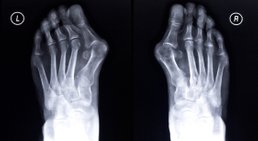

Hallux valgus

Der Hallux valgus ist eine fortschreitende Erkrankung des Vorfußes und die häufigste Fehlstellung der Zehen. Beim Hallux valgus ist die Großzehe nach außen...

Fußchirurgie: Hammerzehen, Hallux valgus (Schneiderballen), Hallux rigidus, Spreizfuß, Einlagenversorgung mit Gipsabdrücken, Fersensporn, Achillessehnenschmerz /-riss, Ermüdungsbruch,….. Operationen: (ambulant in der Gruppenpraxis) Hammerzehen-OP, Hallux-Operation, Morton Neurom - OP